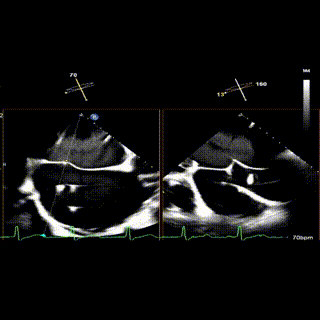

术前TEE评估

术前瓣膜介入团队的心超医生陈星星医师王良国医师对患者的心脏结构和瓣膜解剖情况进行详细的评估:

1.二尖瓣重度关闭不全(4+),瓣环明显扩大(AP径4.6cm,LM径3.9cm),扁平,关闭时瓣叶对合不佳(carpentier I),1-3区均可见反流束,返流宽度达26mm;肺静脉频谱呈收缩期反向。

2.画迹法测得二尖瓣瓣口面积约8.8cm²。

3.PISA法测得EROA=0.57cm²,Rvol=77ml,r=11mm。

4.二尖瓣前叶(A2)长度29mm,后叶(P2)长度11mm。

5.左房巨大(三径86*84*114mm),右房巨大(内径114*86mm),CFI提示极重度三尖瓣反流,Teich法测得EF为70.1%。

3区

怎么上穿刺鞘攻克巨大左房伴转位穿刺难关!温医大附一院周浩教授团队创新应用“导丝定位+可调弯鞘”技术完成高难度TEER手术_https://www.jmylbn.com_新闻资讯_第7张

3区带彩